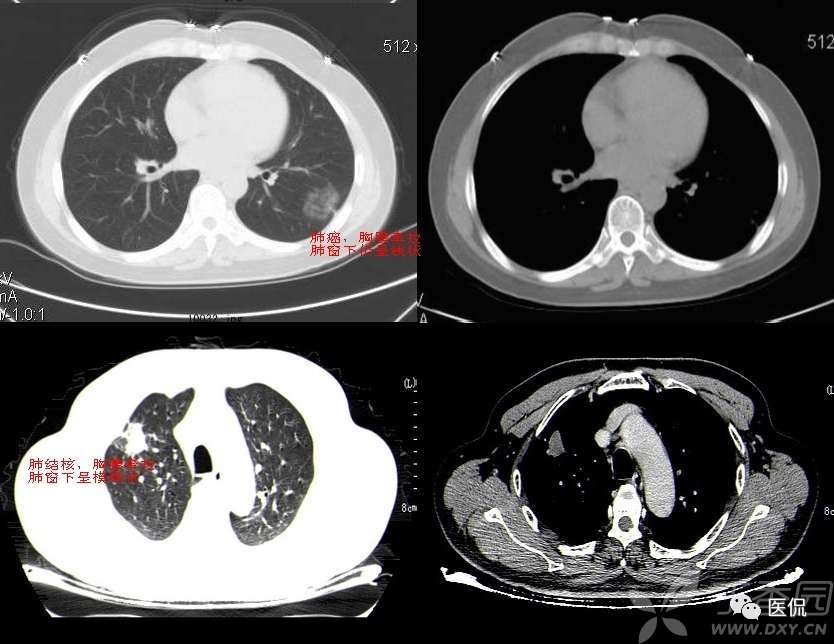

胸膜下弧线(SCLC)

肺胸膜下弧线影像(SCLS)的病理基础

国外学者对此征象的CT与病理对照研究指出,SCLS是细支气管周围纤维性增厚及肺纤维化引起的肺泡变扁和肺不张。构成SCLS的肺不张为肺脏皮质与髓质交界处的盘状肺不张,肺不张的发生与肺间质纤维化后肺脏的顺应性减低有关。指出肺脏蜂窝状改变的边缘融合也可形成SCLS,SCLS位于蜂窝之间,这在HRCT图像上可清楚地显示。临床发现,SCLS发生在慢性肺炎之后,少数发生在慢性支气管炎合并肺间质纤维化患者吸气不足状态,深吸气时大部分消失,也有发生在阻塞性肺不张后,这些表明SCLS为肺脏局部通气不良发生的盘状肺不张。胸膜广泛钙化,SCLS与胸膜钙化的范围一致,肺内也有轻度的肺间质纤维化改变,胸膜钙化可能使胸膜下肺策划的顺应性下降,从而对SCLS的形成有促进作用。胸膜增厚与胸膜结节也可能引起类似的结果。

SCLS的HRCT形态特点

SCLS与生理性的肺下垂部线性影像不同,生理性胸膜下线位于肺脏的最低部,在仰卧位时位于下叶后部,而转变为俯卧位时下叶后部的线性影像消失,生理性胸膜下线多距胸膜下5mm以内,可合并局限性肺脏密度增高。而SCLS虽然在肺脏后部多见,但多超过一个肺段的范围,并可位于肺脏非下垂的部位。体位变换时其形态无变化,也不会消失。多数SCLS表面光滑、呈连续状,少数为不规则及不连续状。煤工尘肺的SCLS可有结节状影,或厚度较大。

SCLS的诊断意义

SCLS可见于多种肺间质纤维化的疾病,如慢性支气管炎合并肺间质纤维化,煤工尘肺,特发性肺间质纤维化,胶原病引起的肺间质纤维化,及结节病引起的肺改变等。慢性支气管炎,特发性肺间质纤维化,煤工尘肺及胶原病引起的肺脏改变等均可出现,占90.3%。以往一些作者曾认为SCLS在石棉肺多见,或认为此征象是石棉肺病人的特有表现。但临床研究的结果表明,SCLS是肺间质纤维化的一种常见征象,见于多种疾病。此外,SCLS还见于炎症、肺瘀血和吸气不足状态。对于肺间质纤维化的病例,SCLS为肺间质纤维化的早期改变。

SCLS周围无肺间质纤维化征象者占25.71%,仅有小叶内间质增厚及小叶间隔增厚者占28.57%,发生较多蜂窝改变的仅占20%。SCLS的长度与肺间质纤维化的严重程度有关,有人对随访的肺间质纤维化逐渐加重的患者,发现SCLS也由短线型发展为长线型。即使SCLS可发生在有蜂窝的部位,但蜂窝改变多较轻微,而在蜂窝改变较密集之处未能见到SCLS。有研究指出,SCLS开始发生在肺间质纤维化轻微的部位,5年后该部位发生严重蜂窝改变,SCLS则不能显示。这表明SCLS的发生、延长与肺间质纤维化加重有关,但出现严重蜂窝后SCLS则不能显示。

总之,SCLS可以变小或消失,表明SCLS有些为可逆的改变。不同的疾病SCLS在形态上多无显著的差异。煤工尘肺SCLS可有细小结节,此结节与肺内结节的形态相似,代表了煤工尘肺的形态特点。但对大多数疾病而言,SCLS缺乏鉴别诊断价值。